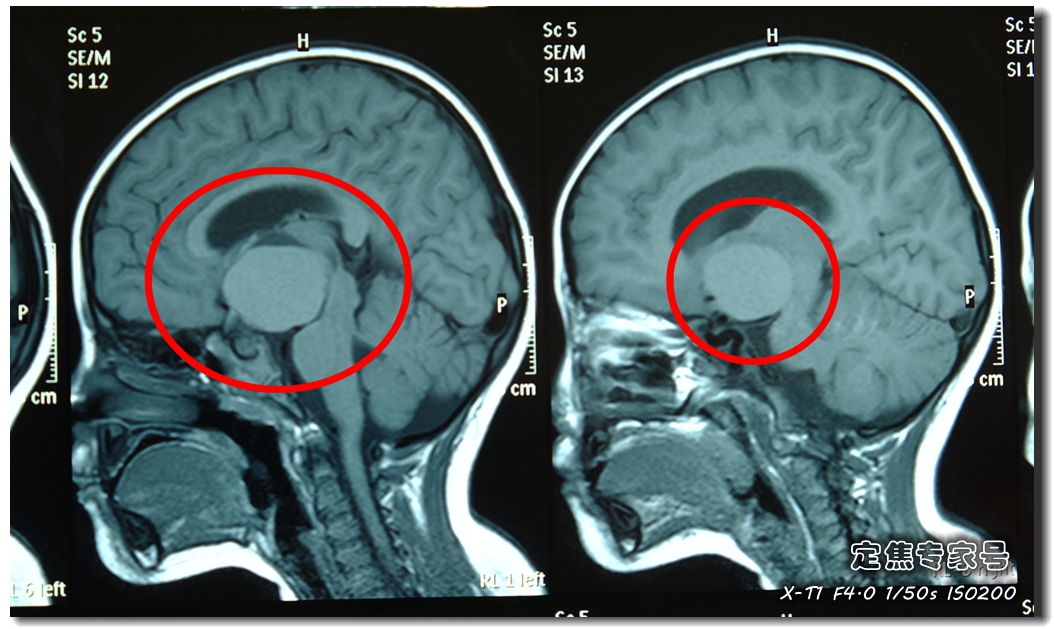

核磁片子下,真相大白。

一个直径将近4厘米的大瘤子,横在蓉蓉的颅脑中央!

吴斌,副教授,首都医科大学三博脑科医院副院长,知名神经外科专家。他判断,蓉蓉是儿童常见的颅咽管瘤。

颅咽管瘤多见于儿童及少年, 肿瘤大多位于鞍上区,也就是眉心中间向后的颅脑中间位置。